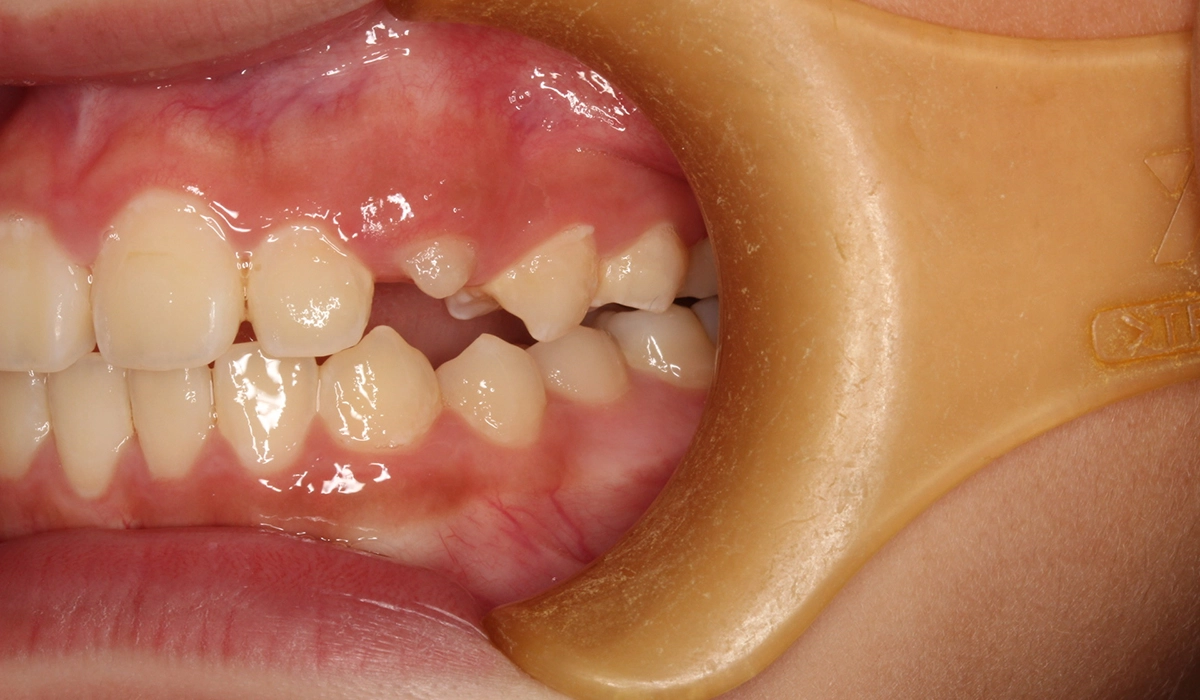

術前:右側